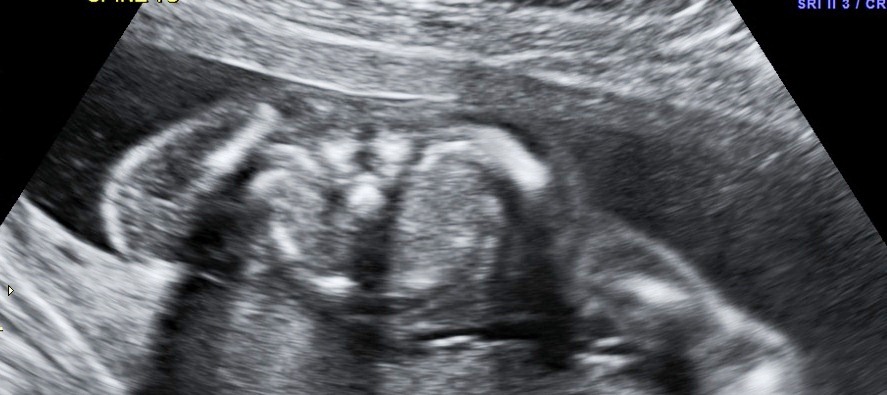

:think:Attachment 5482 BITS OR BONES?

Its gotta be bones the back two round things but what about the front one?

No idea, spine maybe?